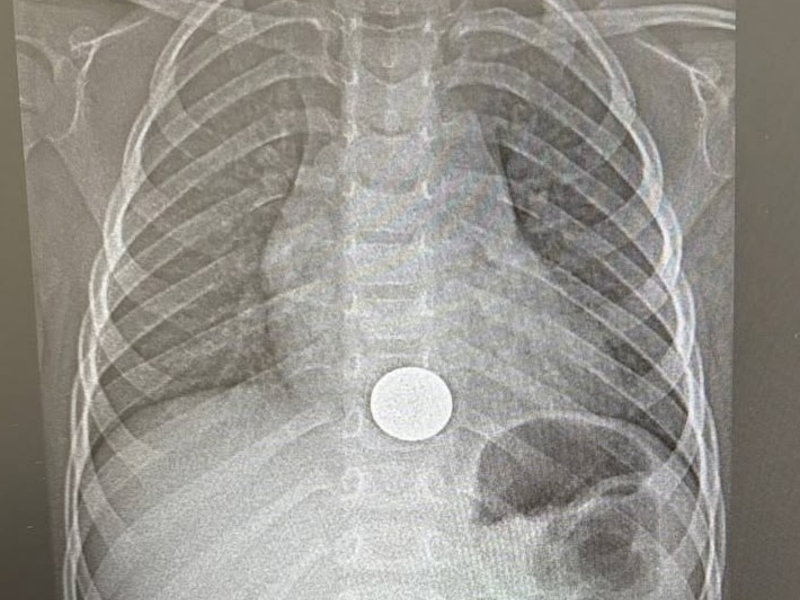

В Нижнекамской больнице помогли ребёнку, проглотившему монету